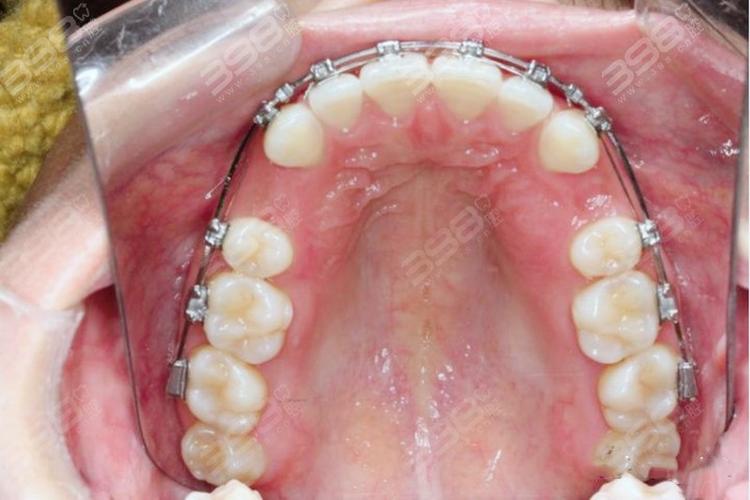

拔牙后开始戴矫正器(如传统托槽矫正器、隐形矫正器),需注意: